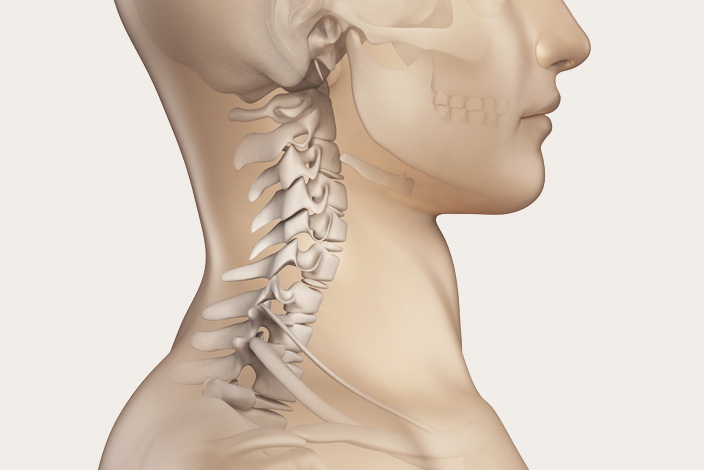

목디스크란 목뼈 사이에 있는 디스크가 손상되어 신경을 압박하는 질환을 의미합니다. 디스크는 젤리와 같은 수핵과 섬유륜으로 구성되어 있습니다. 섬유륜이 손상되면 수핵이 밖으로 밀려나와 신경을 압박하게 됩니다.

목디스크는 주로 잘못된 자세, 과도한 스트레스, 외상 등으로 발생합니다. 잘못된 자세로 장시간 컴퓨터를 사용하거나 운전을 하면 목에 무리가 가고 디스크가 손상될 수 있습니다.

또한 과도한 스트레스는 근육을 긴장시켜 디스크에 손상을 줄 수 있습니다. 외상은 교통사고, 운동 중 충격 등으로 목뼈가 부러지거나 골절되면 디스크가 손상될 수 있습니다.